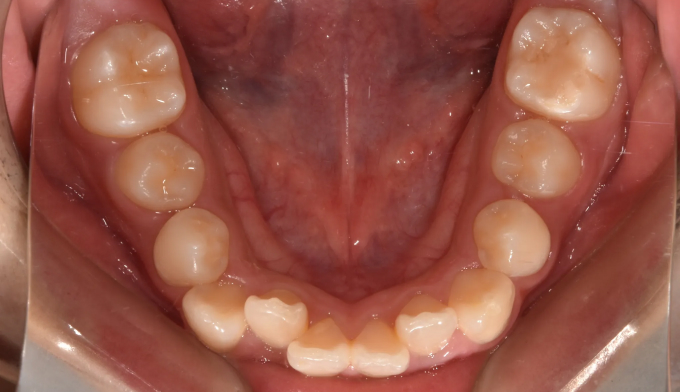

위턱, 아래턱 모두 치아 배열 공간이 부족한 경우 입니다.

확장장치를 이용해 공간 부족을 해결하고 치열을 배열하면 간단히 끝낼 수 있습니다.

이때 입술의 두께나 위치, 위아래 앞니의 각도를 종합적으로 고려하여야 합니다.

치아를 배열한다고 앞니가 뻐드러지면 잘못된 교정치료입니다.

총 치료기간은 20개월 소요되었습니다.